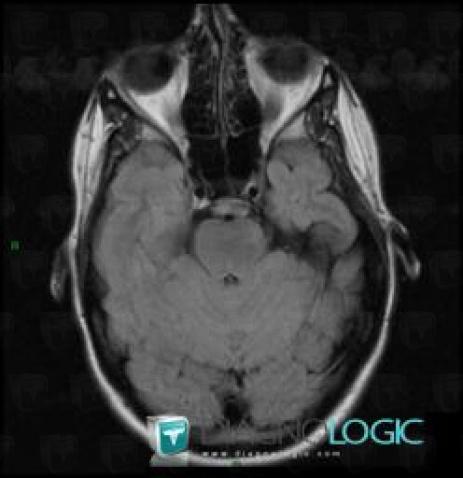

Télangiectasie capillaire, Fosse postérieure, IRM

Voici les informations spécifiques à l'image clé ci dessus:

- Diagnostic Télangiectasie capillaire, Localisation(s) Fosse postérieure, comportant les gammes